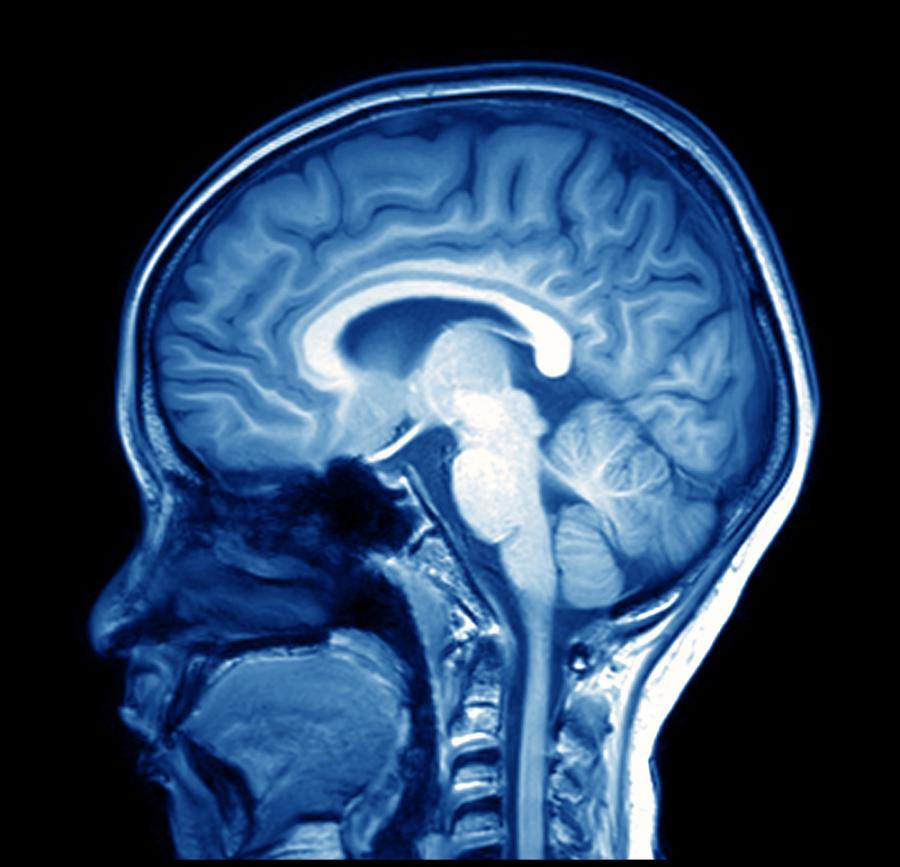

„Мозъчен“ вместо пръстов отпечатък?

Човешкият мозък реагира на различни дразнители по един наистина уникален начин. При това до такава степен, че това негово свойство би могло да се използва за разпознаване на хората.

Сега учените са разширили своя експеримент. Думите са заменени с изображения, а броят на участниците е нараснал на 50. В експеримента на доброволци били показани 500 снимки на предмети, които да предизвикат специфична реакция в мозъка. Сред изображенията били такива на храна, известни личности и думи. Използвайки компютър, който да сканира електроенцефалограмата (ЕЕГ) на участниците, учените успели да разпознаят всеки човек по мозъчната му биометрия с ниво на прецизност от 100%.